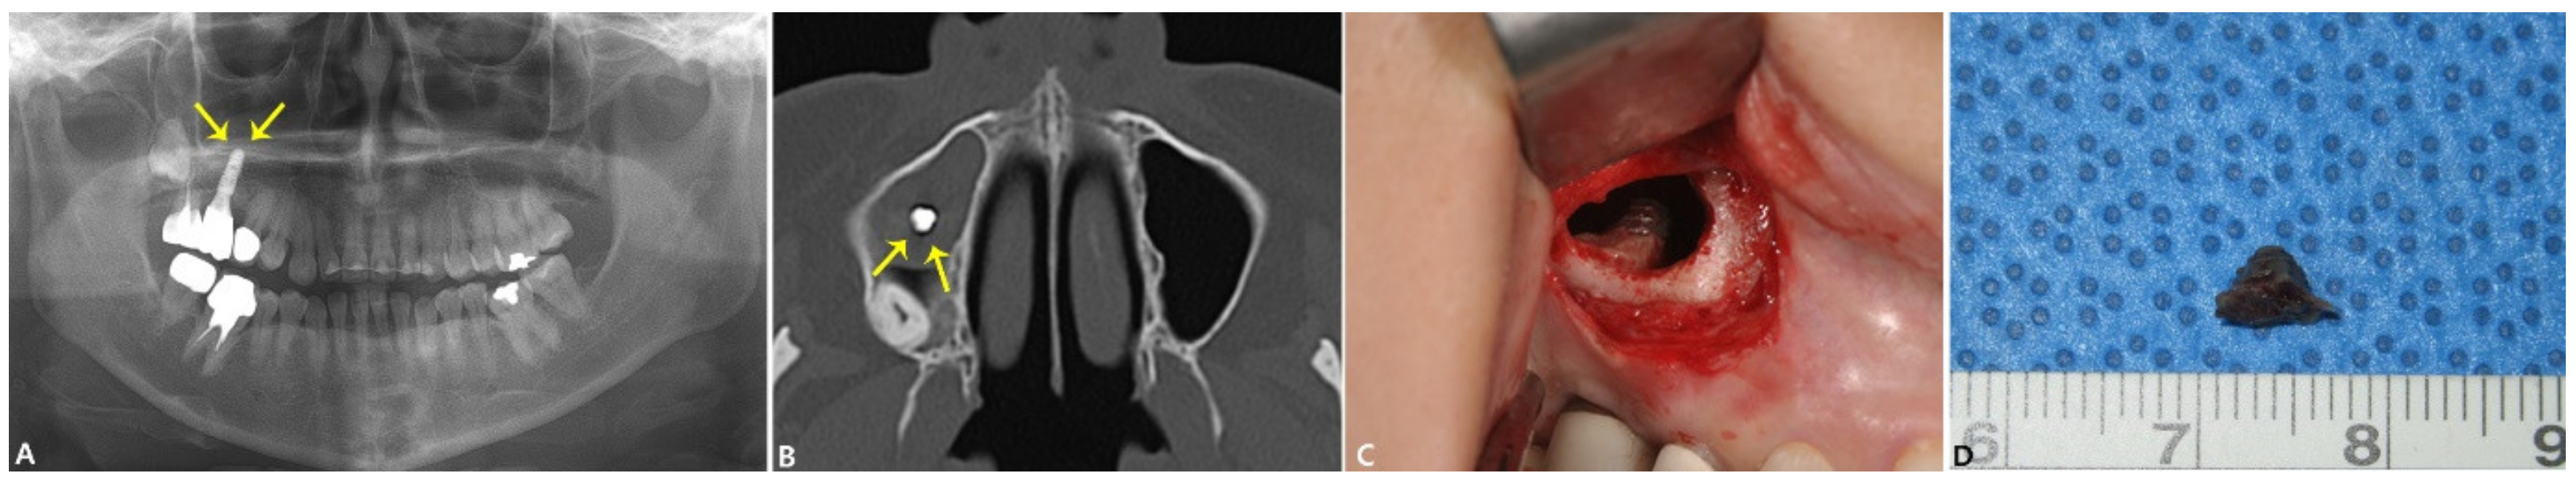

2.1.2. Case 2: Fungal Sinusitis with Involved BRONJ Case

| No. 2 | Fungal maxillary sinusitis | #26i | Bone tissue in the middle region (0204-M) | Ca: 40.75% O: 31.06% Au: 14.17% | Si: 7.14% Na: 5.87% Ti: 1.01% | Detected fungal hyphae in the implant apical region. | |

| High level of Ca, but no detection of Ca. High level of Au, minor sign of Ti | |||||||

| Implant surface in the apical region(0205-A) | Ti: 67.03% Au: 15.68% O: 12.57% | Si: 1.9% Ca: 1.71% Na: 1.1% | The SEM image showed irregular bone tissue with no presence of cell and bone lacunae | ||||

| Ti level was within the normal range Au was detected at a high level Minor signs of Si, Ca, and Na | |||||||